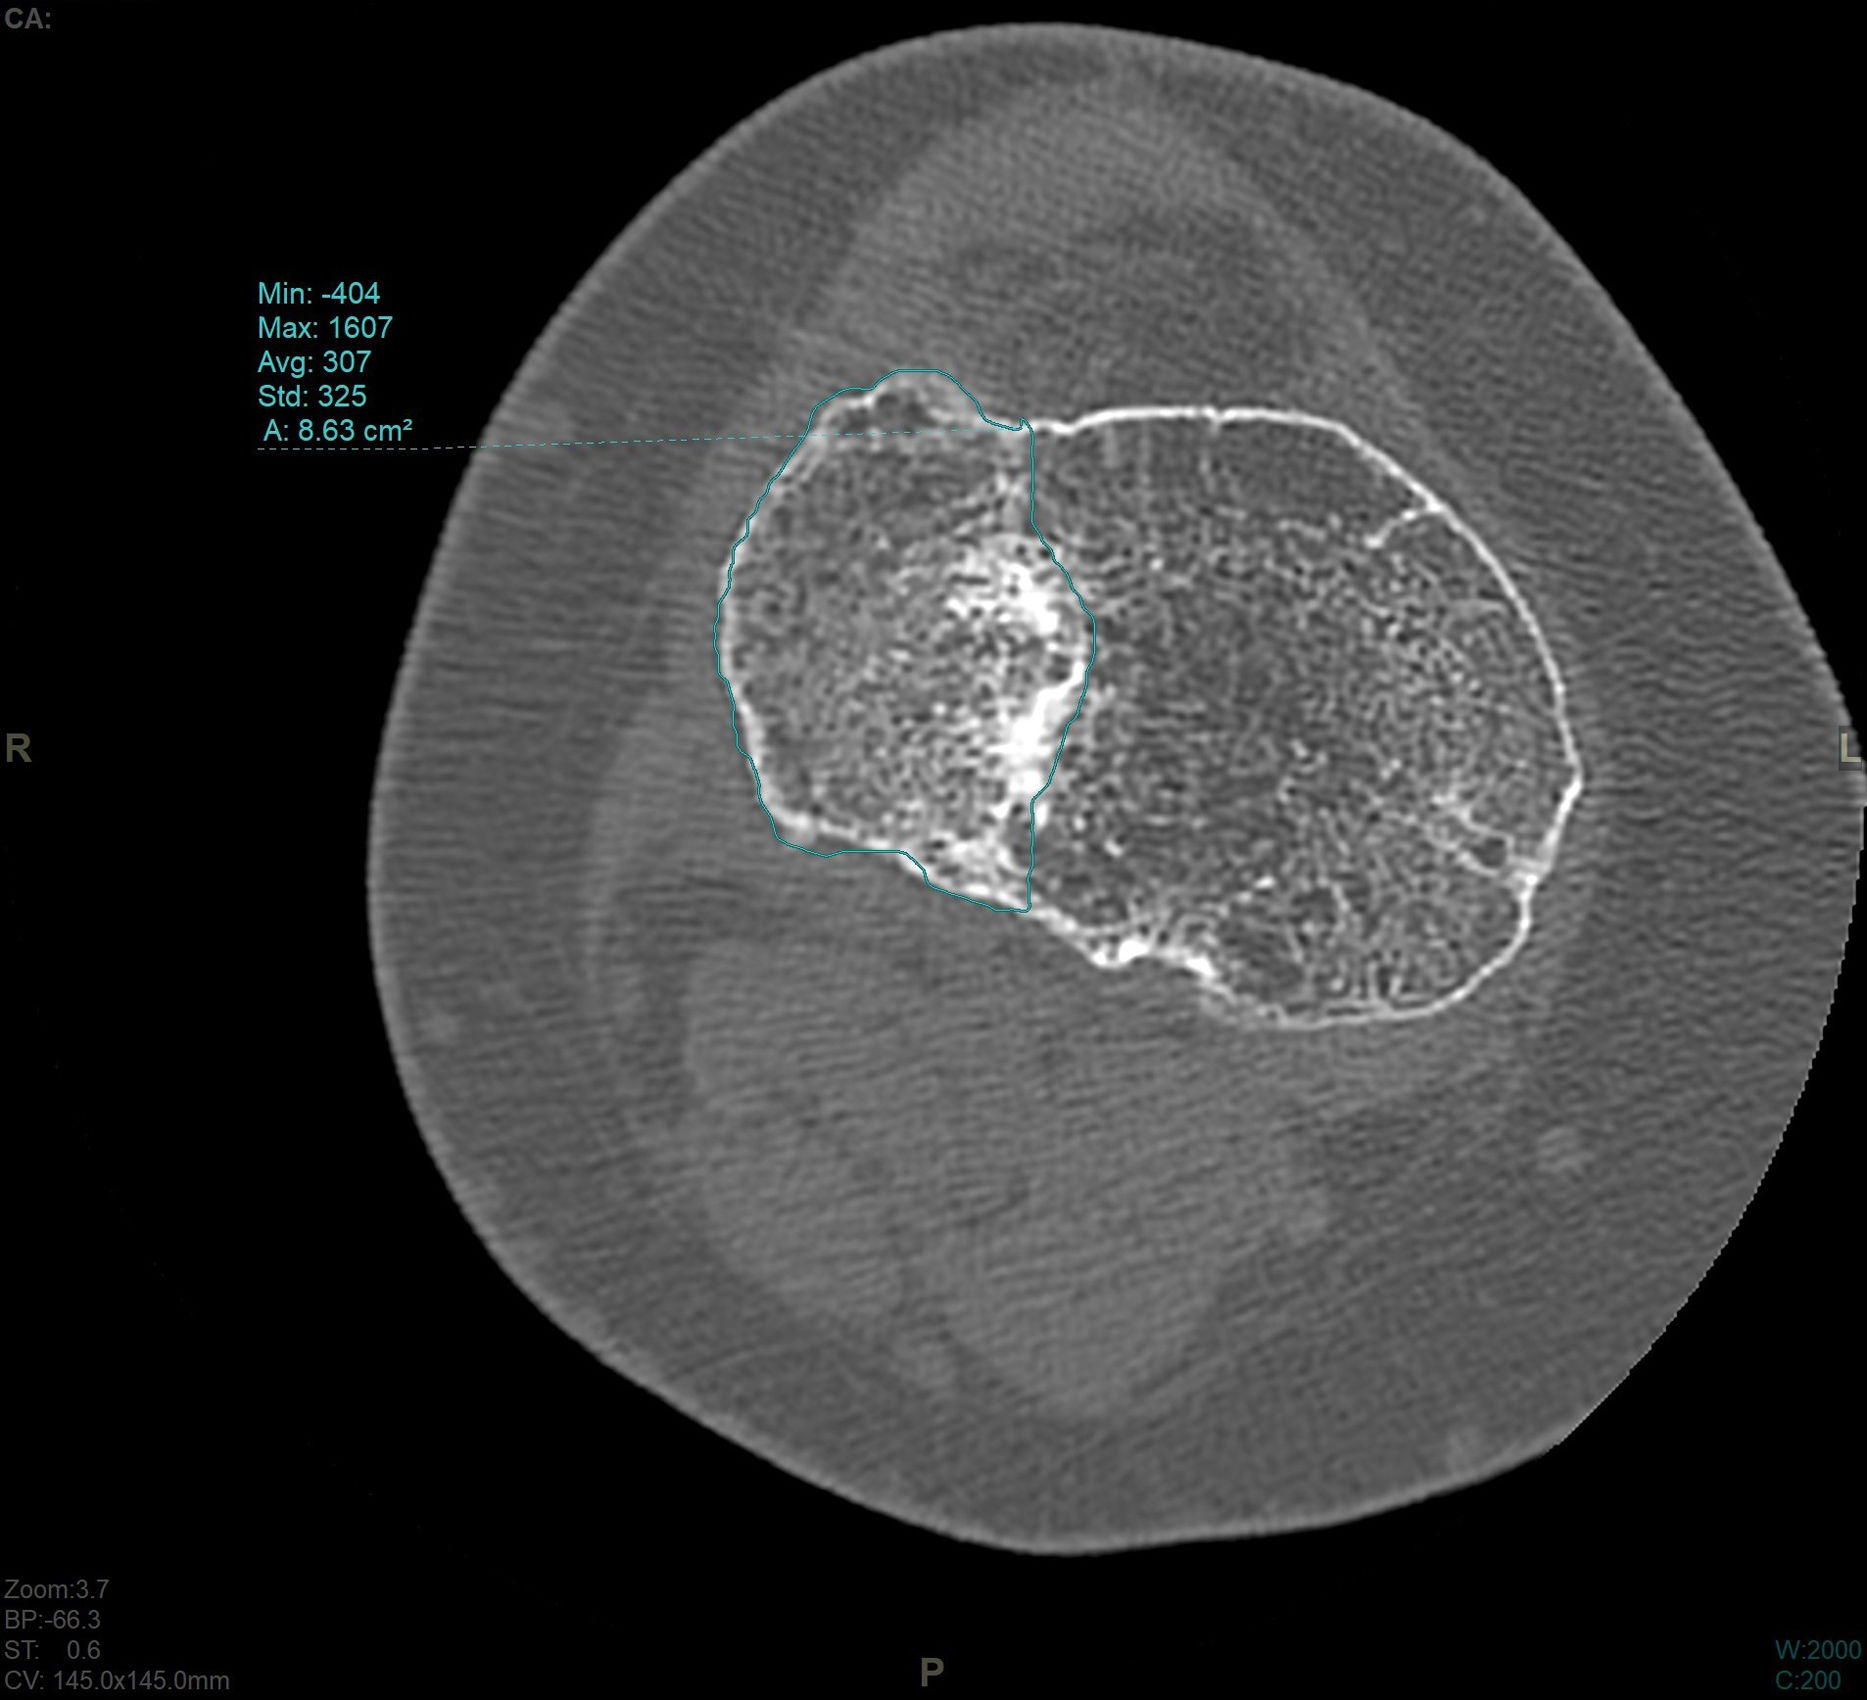

In the CT study, volumetric acquisition was performed using a multi-slice scanner at .6mm thickness, followed by multiplanar reconstruction at 1.5mm slice intervals. In coronal plane reconstruction, the point of greatest fracture depression in millimetres, corresponding to the maximum joint step, and the maximum width/transverse diameter in millimetres were analysed. In the sagittal plane, the maximum anteroposterior joint step diameter in millimetres and the maximum external tibial plateau slope in degrees were measured (Fig. 3). Post-processing in the axial plane involved delimiting the fracture contour and calculating the affected area in cm2, as well as determining the maximum anteroposterior and transverse diameters in mm (Fig. 4).

The mean step measured on CT was 3.6mm (SD: 1.9mm). The mean area measured on CT was 17.57cm2 (SD: 6.1cm2). The mean slope was 12.3 degrees (SD: 5.3 degrees).

| Area (cm2) | 17.57 | 6.1 | 15.16 | 19.99 | 6.32 | 32.43 |